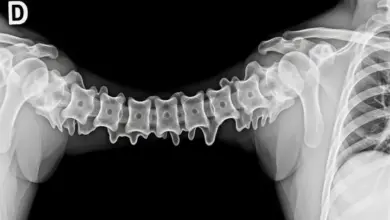

- Ressonância magnética: melhor exame para ver medula, canal vertebral, raízes nervosas e partes moles.

- Tomografia: ajuda a entender a destruição óssea e planejar a cirurgia.